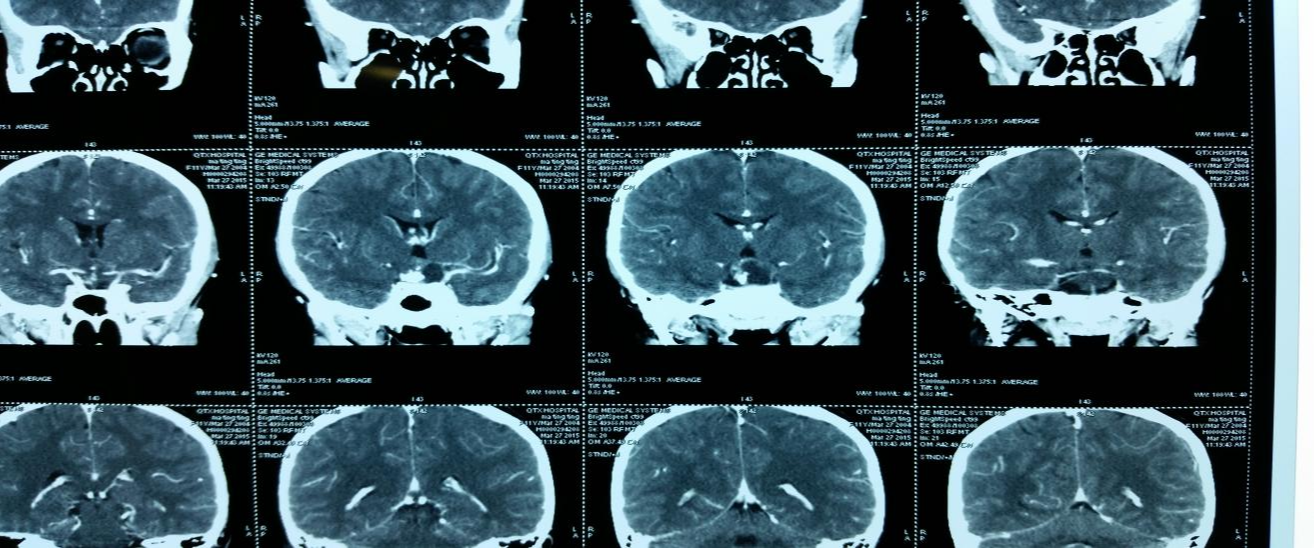

腦干出血5毫升,一般能夠恢復(fù)到四肢活動(dòng)的情況,但是有可能四肢的協(xié)調(diào)性并不好,不能夠恢復(fù)到正常的水平。腦干出血后可能會(huì)出現(xiàn)腦水腫或者顱內(nèi)壓,一定要引起重視,及時(shí)去醫(yī)院進(jìn)行檢查和治療,這一時(shí)期患者還可能會(huì)出現(xiàn)意識(shí)障礙,需要及時(shí)的使用脫水的藥物進(jìn)行調(diào)理,必要時(shí)還要及時(shí)進(jìn)行手術(shù)治療,術(shù)后還要注意做好日常的護(hù)理工作。

結(jié)核性腦膜炎這種疾病的診斷,首先要接受頭顱CT檢查以及核磁共振檢查,然后再結(jié)合患者的一些相關(guān)臨床癥狀以及體征來(lái)做一個(gè)綜合性的分析,倘若存在高度可能性,就需要接受腦脊液檢查,可以找到結(jié)核菌,那么就可以確診結(jié)核性腦膜炎。

出現(xiàn)這樣疾患的時(shí)候,可實(shí)施腰穿,做下腦脊液檢查措施,結(jié)核性腦膜炎患者還有腦脊液出現(xiàn)的異常變化,是有很大特征性的。其中也可以采用腦脊液做下結(jié)核菌涂片、培養(yǎng)檢查,而從腦脊液之中,培養(yǎng)結(jié)核桿菌,那么結(jié)核性腦膜炎是否確診就明確了,也可磁共振檢查。